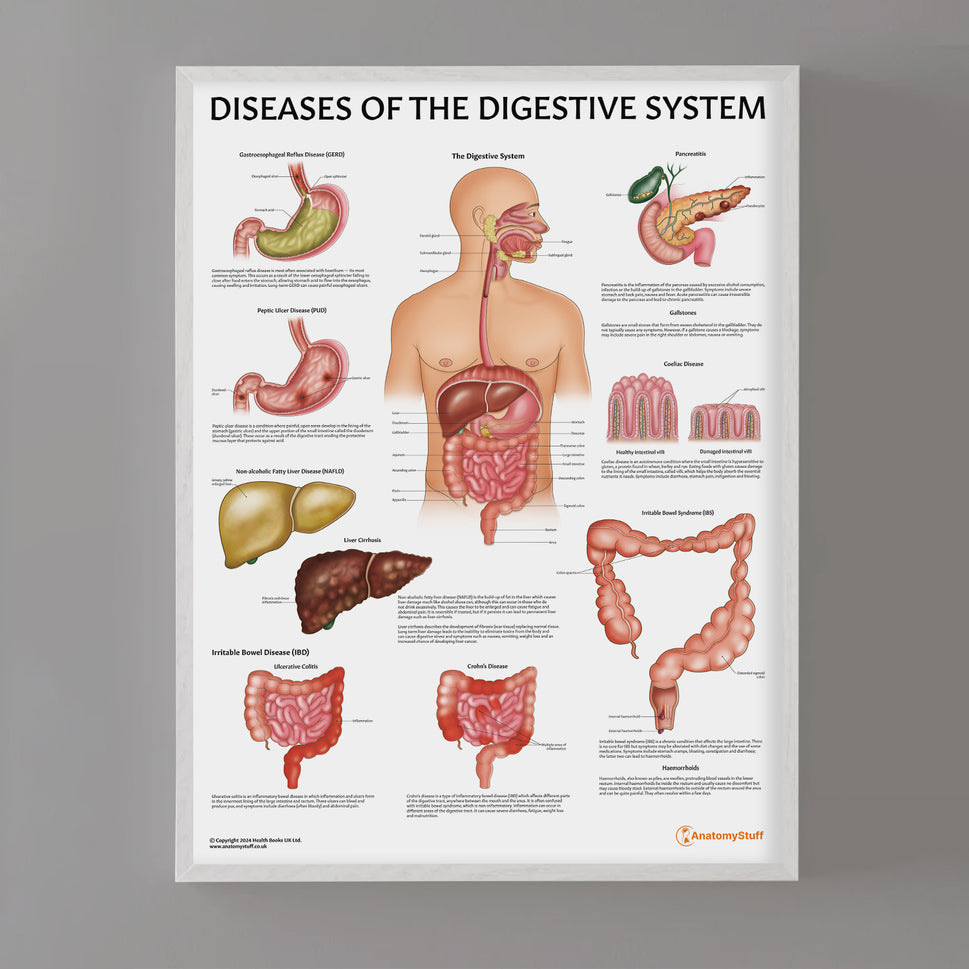

Enhance medical education with our collection of digestive system anatomical models including the stomach, liver, gallbladder, pancreas & colon models. Discover the anatomy of healthy organs as well as common gastrointestinal diseases such as stomach ulcers, gallstones and liver cirrhosis. Our digestive system anatomy posters are ideal for study and patient education.

At AnatomyStuff we stock a diverse range of digestive system anatomical models to suit your training needs. From budget models and affordable medical education posters to highly advanced 3D printed bowel models, you can transform medical training and patient education. As well as our own exclusive collection, we are proud resellers of 3B Scientific, Anatomy Lab, Denoyer-Geppert Science Company, ESP Models, Erler Zimmer and GPI Anatomicals. Explore our exclusive collection of digestive system anatomy charts, posters, fine art prints and digital anatomy study guides. Discover the anatomy of key organs like the liver, stomach, pancreas and bowel as well as the pathophysiology of common conditions like peptic ulcer disease, coeliac disease, IBD and much more. We have anatomy posters suitable for school children all the way up to medical degree level. From a liver anatomy poster to a digital study guide all about common GI disorders, find exactly what you need right here to enhance medical training and patient education.